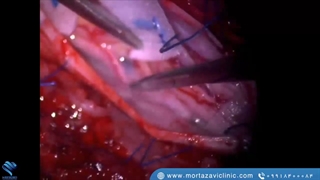

پخش صدا نحوه حرکت در اطراف عصب چشم بدون آسیب رساندن به آن اشتراکگذاری لیست پخش ۰ نظر ۰ نظر دانلود دانلود ویدیو دانلود کیفیت 720p ۶.۱۵ مگابایت دانلود کیفیت 480p ۴.۳۳ مگابایت دانلود کیفیت 360p ۲.۹۵ مگابایت دانلود کیفیت 240p ۱.۷۶ مگابایت دانلود کیفیت 144p ۱.۰۶ مگابایت گزارش تخلف بیشتر گزینههای بیشتر لیست پخش لایکها گزارش تخلف ۰ لایک دکتر مازیار مرتضوی منتشر شده در تاریخ ۱۴۰۱/۱۲/۰۲ این کانال دنبال شد دنبال کردهاید دنبال کردن این کانال دنبال کردن برای کسب اطلاعات بیشتر می توانید به وبسایت https://www.mortazaviclinic.com/ مراجعه کنید. ادامه نظرات لبخند لبخند لغو ثبت نظری برای نمایش وجود ندارد.